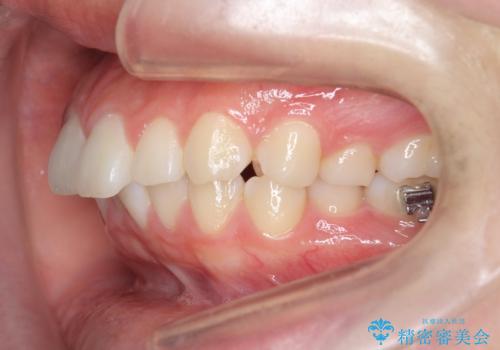

矯正治療を途中でやめてしまった、途中からの治療希望

- 他院での矯正治療中に行かなくなってしまい、装置をつけたまま矯正治療の続きを希望され来院されました。

マウスピースでは並べることが難しい左下の奥歯を部分ワイヤー矯正で並べたのち、マウスピース矯正装置インビザラインで歯並びを整えていきます。